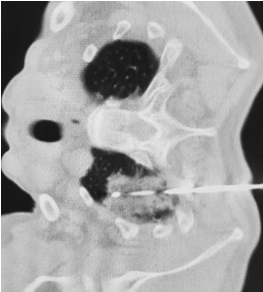

在CT引导下精确设计穿刺点及穿刺路线,从患者后背部肋间隙将氩氦刀消融针准确的穿刺到达肿瘤内,在短时间内极速降温,在针尖周围逐渐形成一个直径约4cm的冰球,将肿瘤病灶完全覆盖,通过3个降温-复温循环,使肿瘤细胞爆裂死亡,彻底摧毁肿瘤细胞组织。术后即刻复查CT显示肿瘤消融完全,达到预期治疗效果。

术中CT引导图像